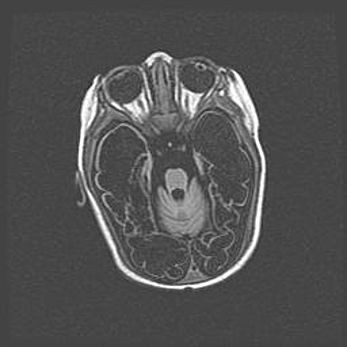

Мальформация Денди-Уокера. Киста задней черепной ямки.

Агенезия мозолистого тела.

Возраст: 2,5 месяца

Вес: 2420 г

Пол: женский

Окружность головы: 37 см

Срок гестации: 32 недели

Мальформация Денди—Уокера — редкий вид патологии ЦНС, представляющий собой врожденный порок развития каудального отдела ствола и червя мозжечка, ведущий к неполному раскрытию срединной (Мажанди) и латеральных (Лушка) апертур IV желудочка мозга. Для этогно синдрома характерна триада симптомов: гипотрофия червя мозжечка и/или полушарий мозжечка, кисты задней черепной ямки, гидроцефалия различной степени. В 70% случаев порок сочетается и с другими аномалиями головного мозга, в частности с агенезией мозолистого тела.